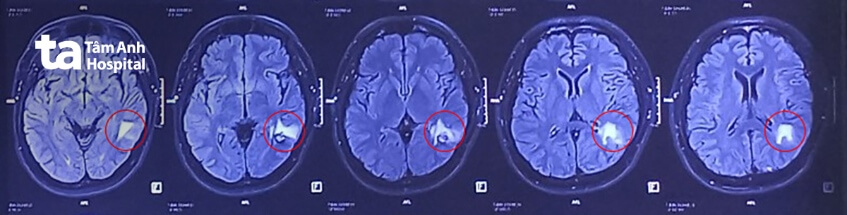

Ngày 16/11, ThS.BSCKII Chu Tấn Sĩ (Trưởng khoa Phẫu thuật Thần kinh, Bệnh viện Đa khoa Tâm Anh TP HCM) cho biết, anh Phúc đến khám từ tháng 6/2023 vì chứng động kinh kháng thuốc (dùng thuốc vẫn không khỏi). Kết quả chụp MRI 3 Tesla phát hiện khối u mạch máu thể hang tại vùng chẩm trái, kích thước khoảng 1,5 cm.

Bác sĩ nhận định, thành mạch máu tại khối u không chắc, dễ vỡ, nguy cơ cao dẫn tới xuất huyết não. Bệnh nhân được tư vấn điều trị bằng phẫu thuật nhưng lo lắng biến chứng, tiếp tục chọn dùng thuốc chống động kinh với liều cao nhất.